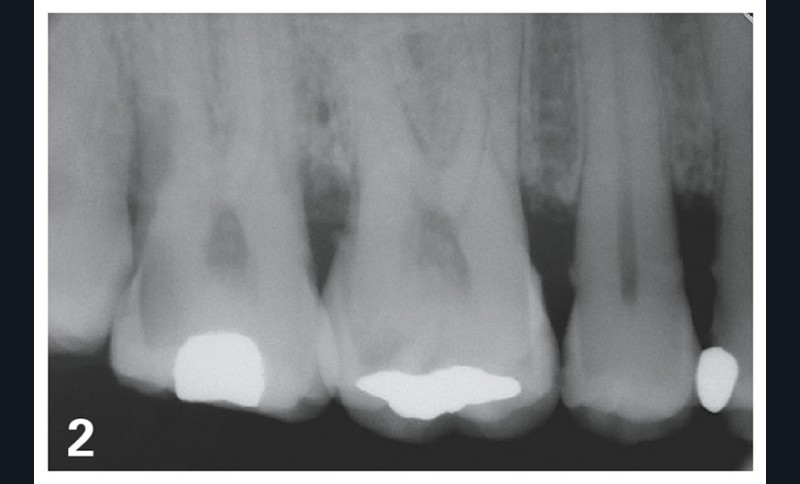

Dans le cas illustré par les figures 1 à 4 ci-dessus, les 16, 17 et 36 doivent être soignées et restaurées. Le choix des onlays permet :

– une solution économe en tissus dentaires ;

– une liberté d’honoraires ;

Le choix de trois couronnes périphériques aurait nécessité de présenter au moins une alternative en RAC-0, en l’occurrence des couronnes métalliques. Bien entendu, de nombreux patients auraient refusé et auraient choisi une option plus esthétique. Les honoraires auraient cependant été plafonnés pour cette option RAC-0.